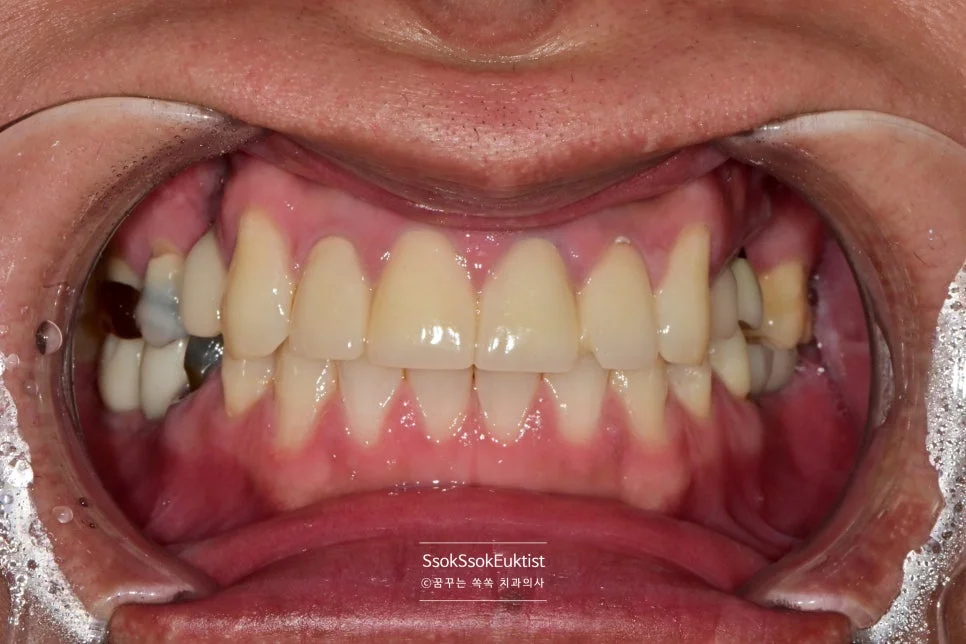

치료 전 정면 구내사진 — 다수의 치아 문제가 보이는 상태

사진에서 1번, 4번 치아의 경우 치아 머리가 너무 남지 않아 발치 후 임플란트가 필요한 상황입니다.

자연치아 살리기에 진심인 마곡나루 치과지만 모든 치아를 다 살려서 쓸 수는 없거든요.

1번, 4번 치아의 경우 자연치아 살리기 조건 중 세 번째 조건을 만족하지 못하여 발치의 대상입니다.

한편, 3번의 경우 치아를 발치하고 오랜 시간이 지난 위치로 예쁘게 임플란트 식립을 진행하면 됩니다.

그런데 2번의 임플란트를 한번 보면 뭔가 잇몸이 부자연스러운 것을 볼 수 있는데요.

임플란트 주변에 뼈가 다 녹아내리고 그 바깥에 잇몸까지 혈류를 받지 못해 점점 괴사하고 있는 모양새입니다.